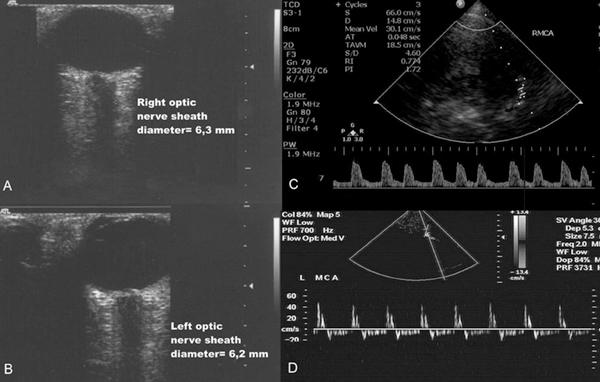

A 42-year-old, previously healthy man was admitted with fever of 39 degrees C, blurred vision, confusion and headache. He had right-sided central facial paresis, bilateral absent gag reflex and bilateral cerebellar ataxia. After a few hours, he became septic and developed bilateral vocal cord paralysis and airway obstruction. He was intubated and put on mechanical ventilation. Computed tomography brain scans revealed multiple frontal hypodense areas and slight hydrocephalus. Cerebrospinal fluid findings included pleocytosis of 4200 cells/muL (77% neutrophils), protein of 114 mg/dL and normal glucose levels. Listerial infection was suspected; therefore ampicillin was added to his initial therapeutic regimen, already including ceftriaxone and gentamicin. All cultures were negative, and no immunologic abnormality could be documented, but the patient's clinical condition deteriorated rapidly. Continuous neuromonitoring by means of transcranial Doppler and optic nerve sonography along with follow-up computed tomography brain scans confirmed the severity of the brain damage; hence, dexamethasone and mannitol were also administered. The patient was clinically documented as 'brain dead' 7 days after his admission to the intensive care unit; thereafter, blood- and post-mortem brain tissue cultures grew Listeria monocytogenes.

一名42岁、既往健康的男性因39摄氏度发热、视力模糊、意识模糊和头痛入院。他有右侧中枢性面瘫、双侧咽反射消失和双侧小脑性共济失调。数小时后,他发生脓毒症,并出现双侧声带麻痹和气道梗阻。他接受了气管插管并进行机械通气。计算机断层扫描脑部显示多个额叶低密度区和轻度脑积水。脑脊液检查结果包括细胞数4200个/微升(77%为中性粒细胞)、蛋白114毫克/分升、葡萄糖水平正常。怀疑为李斯特菌感染;因此在其初始治疗方案(已包括头孢曲松和庆大霉素)中加用了氨苄西林。所有培养结果均为阴性,且未发现免疫异常,但患者的临床状况迅速恶化。通过经颅多普勒和视神经超声进行连续神经监测以及后续的计算机断层扫描脑部检查证实了脑损伤的严重程度;因此还给予了地塞米松和甘露醇。该患者在入住重症监护病房7天后被临床诊断为“脑死亡”;此后,血液和尸检脑组织培养均培养出单核细胞增生李斯特菌。